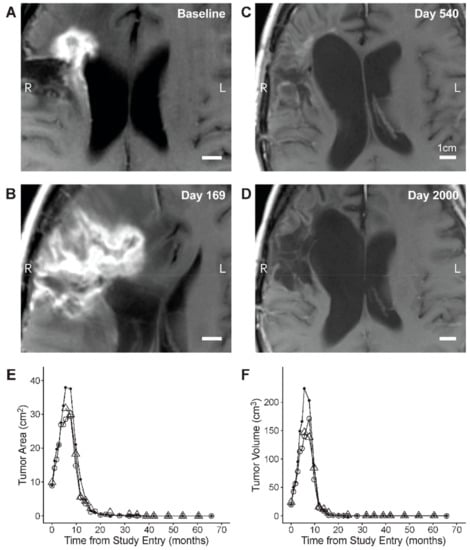

3.3. Edema and Pseudo-Progression in OT101-Yreated Target HGG Lesions